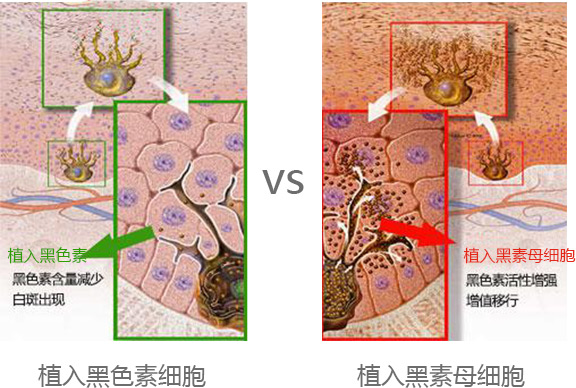

从自身提取的黑素母细胞和黑色素细胞,不会有排斥反应,等于种入了“种子”,能源源不断的生成黑色素。

传统种植则种入黑色素细胞和黑色素,种入的是“秧苗”而不是“种子”,大多造成种植一段时间后,黑色素会被代谢掉,脱失,白斑重新出现。

植入自体黑素母细胞后,黑色素可源源不断生成,均匀 着色。图为成活后的黑素母细胞电镜图。